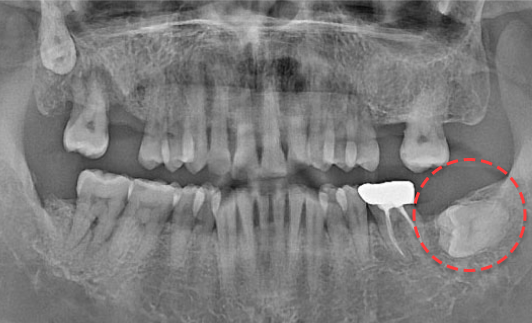

• BEFORE

오른쪽 하악 매복 사랑니 발치 Before X-Ray

치료시작일

2020.04.24

AFTER

오른쪽 하악 매복 사랑니 발치 After X-Ray

치료종료일

2020.06.24

오른쪽 하악 매복 사랑니 발치